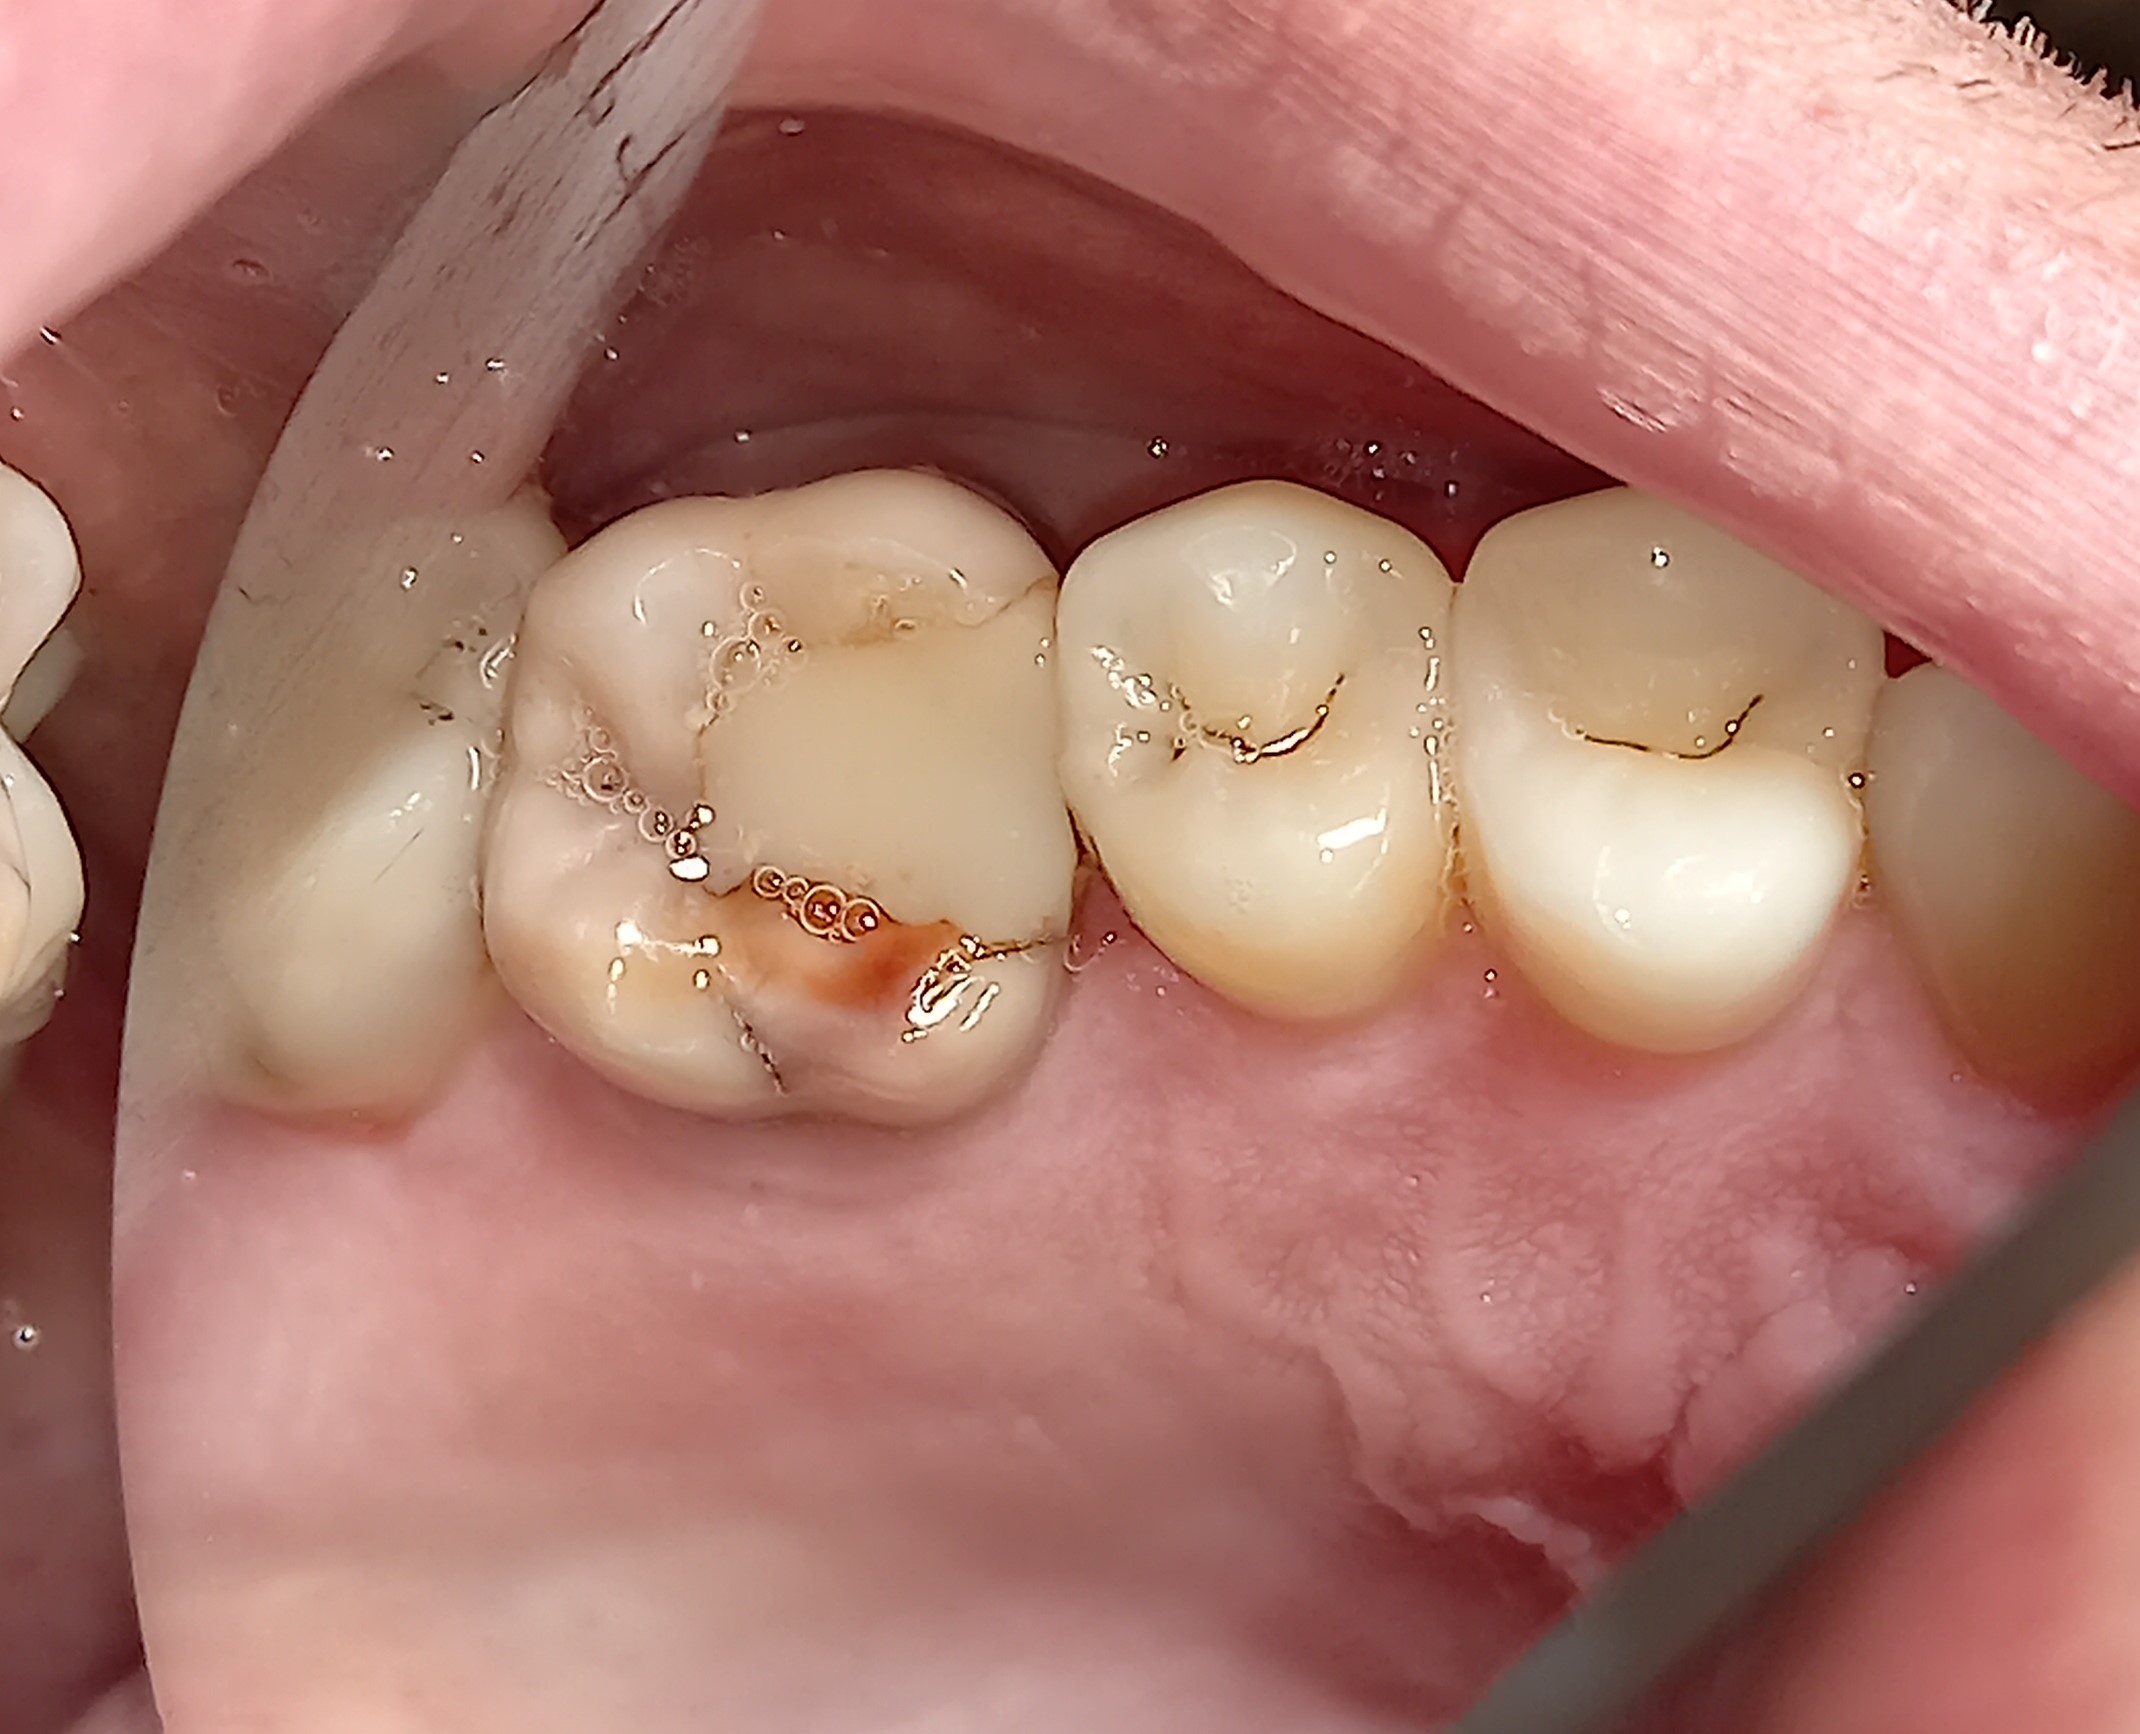

Η ασθενής προσήλθε στο ιατρείο με την επιθυμία να αποκαταστήσει τα δόντια της. Μετά την κλινική εξέταση διαπιστώθηκε στην πάνω αριστερή πλευρά ότι 3 δόντια χρειαζόταν την άμεση οδοντιατρική θεραπεία. Όπως φαίνεται και στις φωτογραφίες στον πρώτο προγόφιο και στο δεύτερο γομφίο υπήρχαν παλιές εμφράξεις ρητίνης (λευκά σφραγίσματα) τα οποία είχαν επανατερηδονιστεί. Μετά τον εκτροχισμο των παλιών σφραγισμάτων, αφαιρέθηκε η τερηδόνα που εντοπιζόταν κάτω από τα σφραγίσματα και τα 2 αυτά δόντια αποκαταστάθηκαν με νέα λευκά σφραγίσματα. Ο πρώτος γομφιος παρουσίαζε ένα εκτεταμένο παλιό σφράγισμα αμαλγάματος και επιπλέον ένα κομμάτι του φυσικού δοντιού είχε σπάσει. Λόγω της εκτεταμένης βλάβης του δοντιού αποφασίστηκε η αποκατάσταση του δοντιού με μία στεφάνη (θήκη) ζιρκονίου.

ΠΡΙΝ

META